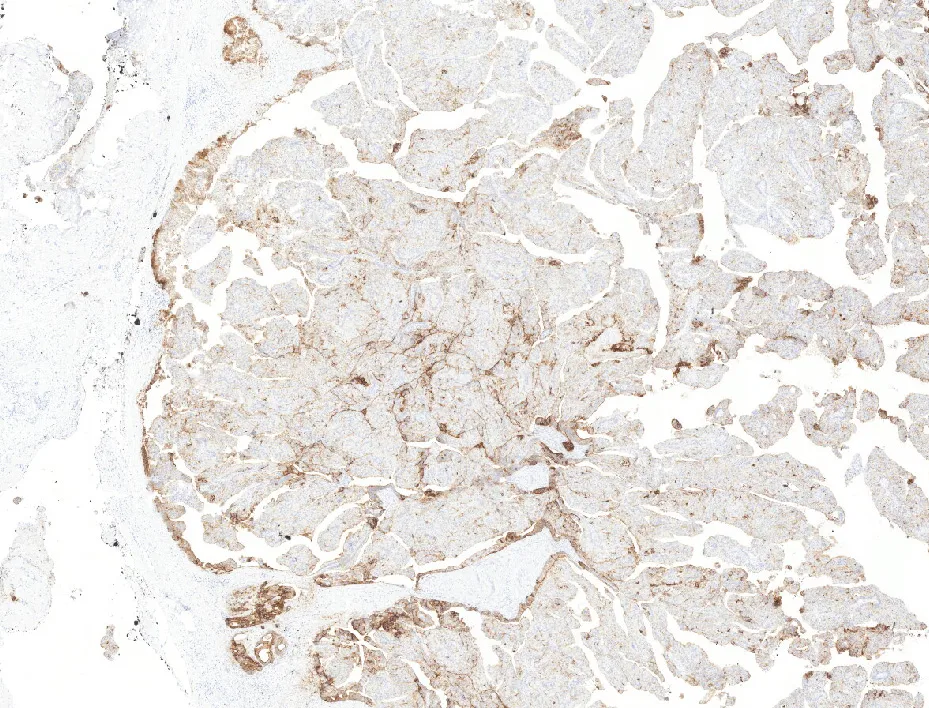

6-CEA

- Histológicamente se caracterizan por áreas quísticas y sólidas con múltiples proyecciones papilares luminales que tienen un núcleo fibrovascular y están revestidas por células epiteliales cúbicas, columnares o secretoras de moco. Inmunohistoquímicamente es CK7, CEA y EMA positivo, siendo negativo para otros marcadores de glándula salival. (PMID: 35252049)